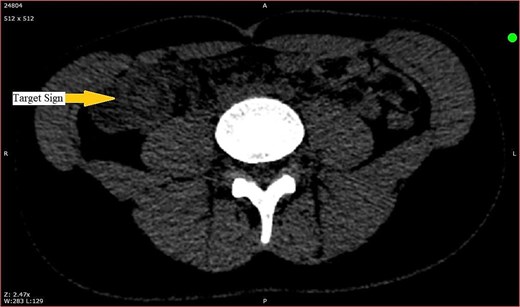

Further laboratory investigations including complete blood count revealed leukocytosis as white blood cells count of 16.4 × 109/l, with neutrophilic predominance, and mildly elevated C-reactive protein of 9.3 mg/l, abdominal ultrasound showed a target sign with dilated thickened appendiceal and cecal wall. A limited noncontrast abdominal CT scan was carried out to localize appendix, that showed a target sign in right iliac fossa, measuring 3 × 3.5 cm, suggesting ileocecal intussusception (Fig. 1), appendix was not visualized, suggesting the possibility of being a leading point in intussusception.

CT scan showing target sign in the right iliac fossa, suggestive of ileocecal intussusception.